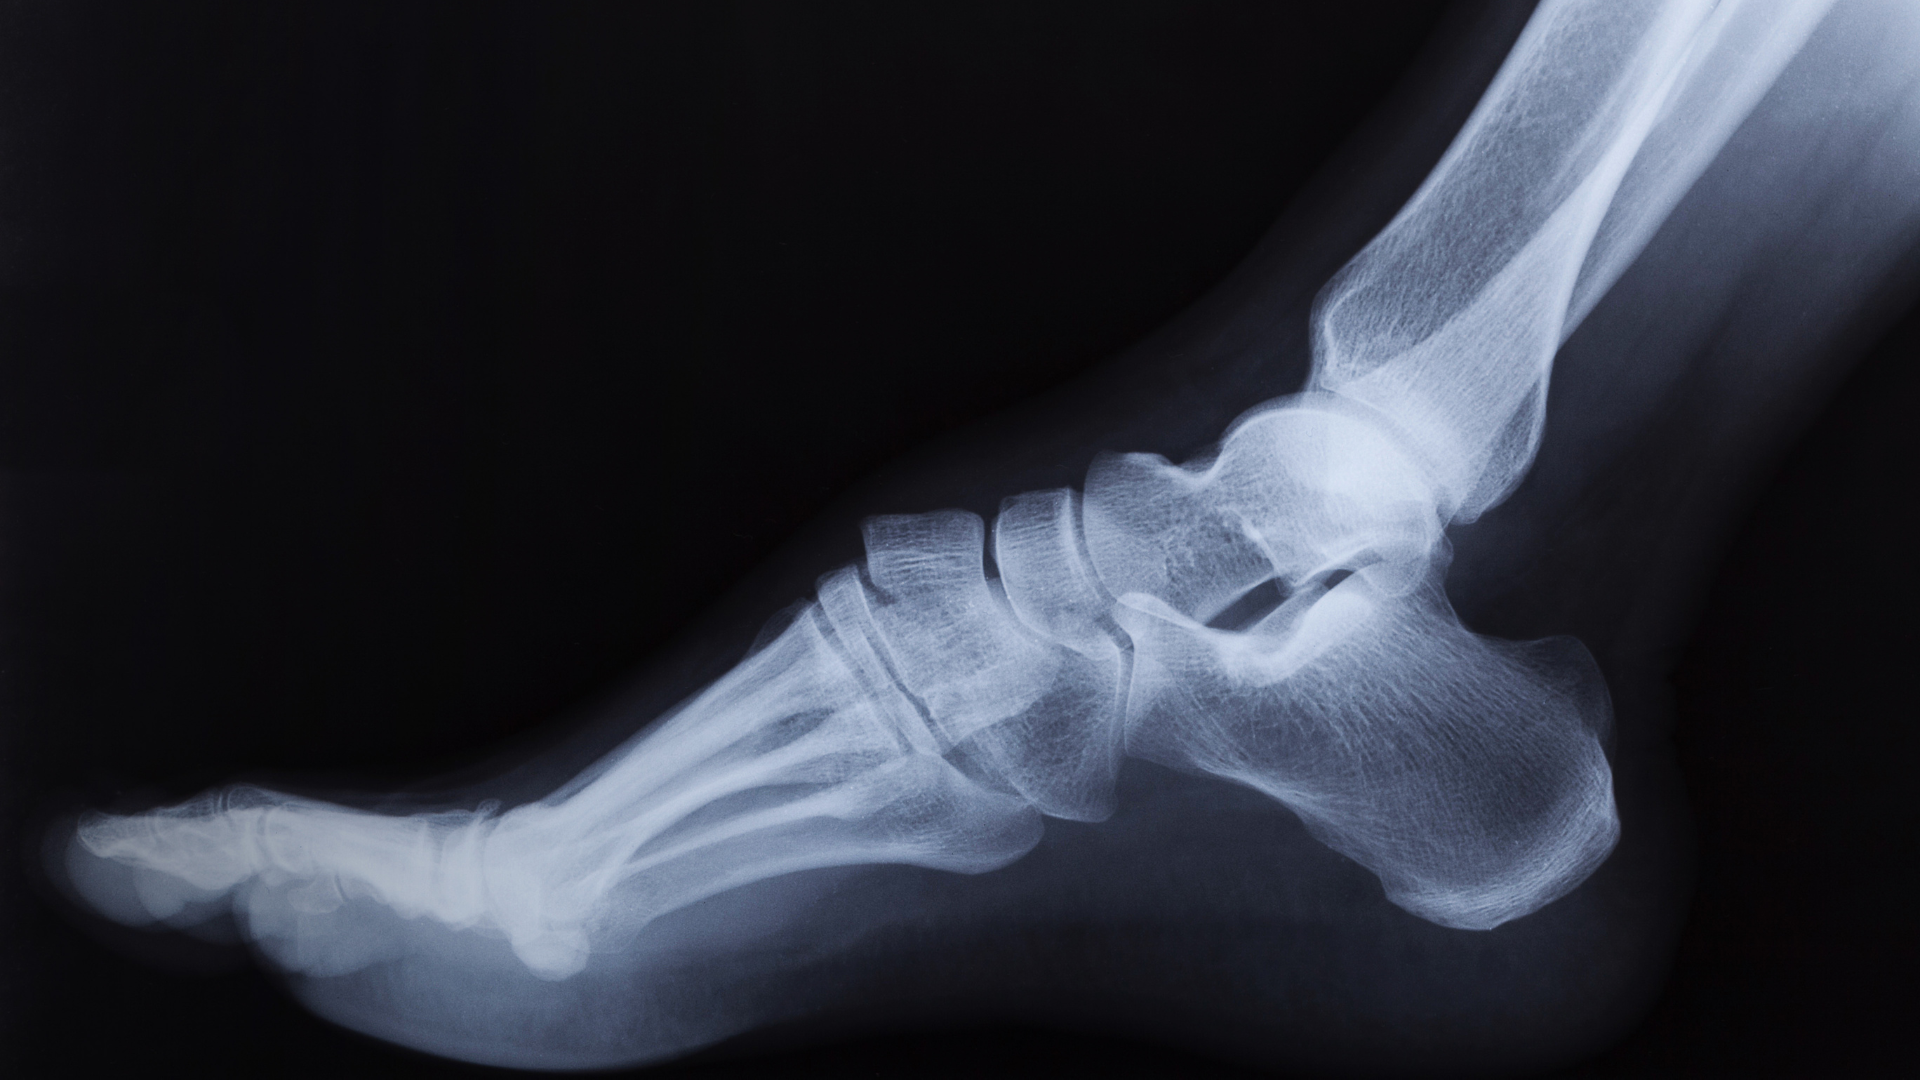

Vị trí và cấu tạo mắt cá chân

Mắt cá chân nằm ở điểm tiếp nối giữa cẳng chân và bàn chân, cấu thành bởi nhiều bộ phận khác nhau:

- Xương: Khớp được hình thành từ ba xương chính là xương chày, xương mác và xương sên. Chúng kết hợp tạo thành ổ khớp vững chắc.

- Dây chằng: Hệ thống dây chằng bên trong và bên ngoài có nhiệm vụ giữ ổn định khớp, giúp ngăn ngừa trật khớp trong quá trình vận động.

- Gân: Liên kết các cơ ở cẳng chân với bàn chân, đóng vai trò quan trọng trong việc gập và duỗi bàn chân.

- Sụn: Bao phủ bề mặt khớp, giảm ma sát khi cử động và hấp thụ lực tác động từ trọng lượng cơ thể.

Chính sự phối hợp nhịp nhàng của các cấu trúc này giúp mắt cá chân vận hành linh hoạt, đảm bảo khả năng chịu lực và duy trì sự cân bằng khi di chuyển trên nhiều địa hình khác nhau.